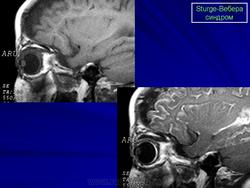

Магнитная резонансная томография пациента с болезнью Штурге - Вебера

Рентгенологически можно обнаружить обызвествление в затылочных и теменных отделах мозга. При ПЭГ у большинства больных отмечаются атрофия вещества мозга, расширение субарахноидальных щелей на конвекситальной поверхности и расширение полостей желудочков мозга.

Диагноз синдрома Стерджа - Вебера не представляет трудностей. Наличие корковых обызвествлений можно выявить при рентгенографии. Характерные тени располагаются в виде двойных контуров, повторяющих извилины пораженных долей мозга. Компьютерная томография выявляет более обширные области обызвествления, чем это видно при обычной рентгенографии.

Магнитная резонансная томография пациента с болезнью Штурге - Вебера